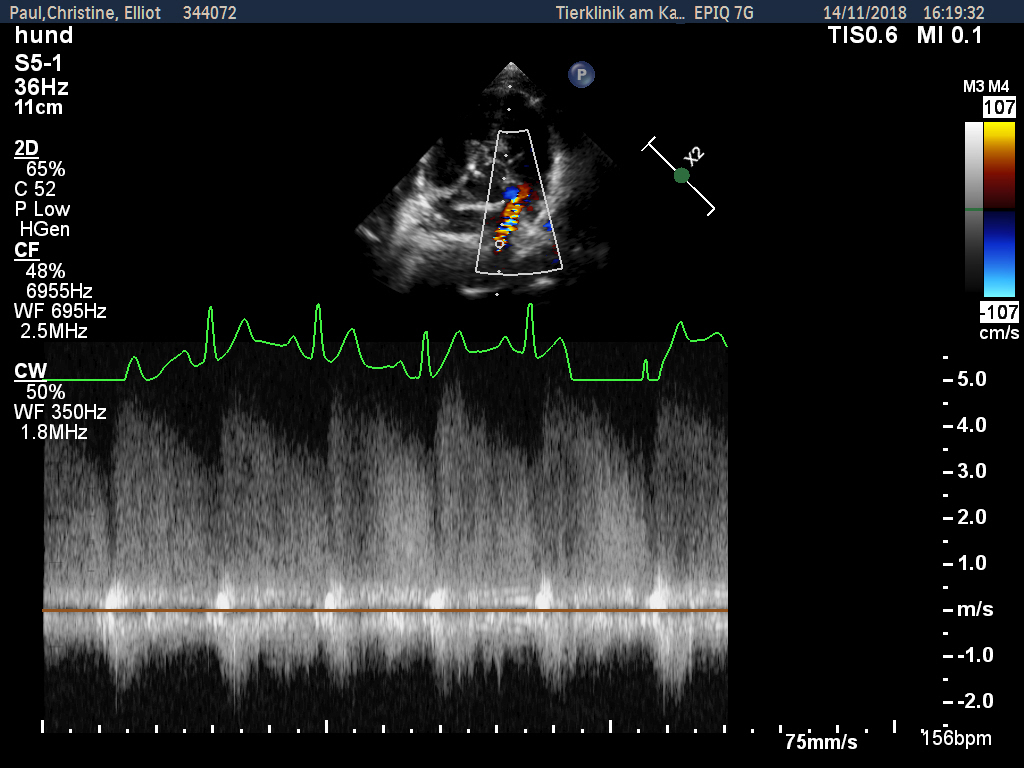

Zunächst wurde von den Kollegen - aufgrund des zeitlichen Zusammenhangs - eine Impfreaktion vermutet, woraufhin Elliot starke Schmerzmittel bekam. Allerdings besserte sich seine Lahmheit weder durch Schmerzmittel noch durch Kortison wesentlich. Da man äußerlich nichts feststellen konnte, wurde eine erste Röntgenuntersuchung des Rumpfes durchgeführt, bei der aber die Ursache leider nicht gefunden wurde. Als auch nach dieser weder Fieber noch Lahmheit verschwanden, wurde der Hund zur Spezialdiagnostik überwiesen. Es sollte nun bei uns in der Klinik erneut geröntgt und eventuell eine Computertomographie durchgeführt werden. Bei der Eingangsuntersuchung vor der notwendigen Narkose wurde ein kontinuierliches Herzgeräusch festgestellt. Dieses konnte nur unter dem linken Schulterblatt in Höhe des 2.-3. Zwischenrippenraumes auskultiert werden. An dieser Stelle war es aber sehr laut (Grad 5 von 6) und gut hörbar. Der untersuchende Kardiologe stellte einen klinisch relevanten PDA (Ductus arteriosus botalli persistens) fest, der sich schon in einem behandlungswürdigen Stadium befand. Daher war an eine Narkose zur Abklärung der Lahmheit an diesem Tage nicht zu denken.

Erfreulicherweise verschwindet die Erkrankung mit Ende des Knochenwachstums. Für Elliot zunächst aber das kleinere Problem. Ein PDA, wie er im Herzen von Elliot festgestellt wurde, verläuft für fast 2/3 der Welpen im ersten Lebensjahr tödlich. Daher muss dieser verschlossen werden. Bei dem PDA handelt es sich um ein Blutgefäß, welches sich nach der Geburt nicht ordnungsgemäß verschlossen hat. Deshalb fließt Blut auch nach der Geburt an der Lunge vorbei zurück in das linke Herz, welches sich daraufhin stark vergrößert.